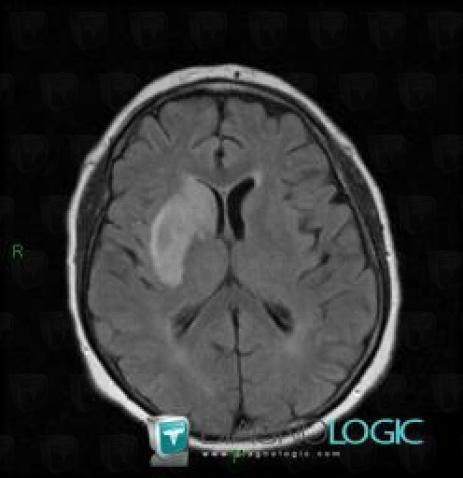

Cerebral infarction, Basal ganglia and capsule, MRI

Here is the specific information in the key image above:

- Diagnosis Cerebral infarction, Location(s) Basal ganglia and capsule, with gamuts DWI hyperintense lesion